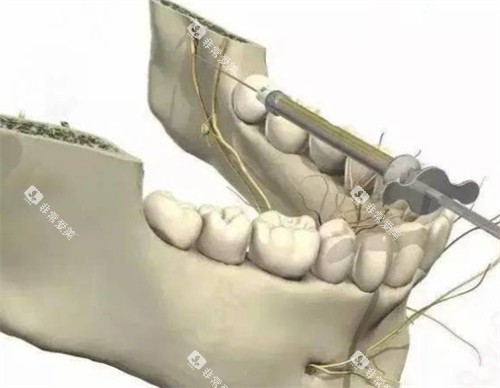

种植牙是目前修复缺失牙比较理想的方式,它能较好地改善牙齿的功能和美观。

张家口市第一医院口腔科的种牙收费受到多种因素的影响。

种植体品牌

不同品牌的种植体价格差异较大。

常见的进口种植体,如瑞士ITI种植体,因其品质优良、稳定性高,收费相对较高,一颗的价格大概在12000 - 18000元左右。

韩国登腾种植体价格相对亲民一些,一颗大约在5000 - 8000元。

国产种植体的价格则更为实惠,一般在3000 - 6000元一颗。

牙冠材料

除了种植体,牙冠的材料也会影响种牙的整体费用。

烤瓷牙冠价格相对较低,一颗大概在800 - 2000元。

全瓷牙冠美观度和生物相容性更好,价格在2000 - 5000元一颗。

患者自身情况

如果患者的牙槽骨条件不佳,在种牙前需要进行骨增量手术等额外治疗,这也会增加种牙的费用,一般骨增量手术的费用在3000 - 8000元不等。